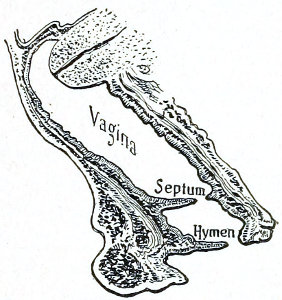

The symptoms of this condition are due to retention of the uterine discharges. There is no discharge of 53 menstrual blood from the vagina. Attacks of pain occur periodically at the menstrual periods. A cystic tumor, which may be felt by rectal examination, is present. The tumor consists of the distended portion of the vaginal canal (hematocolpos), and sometimes of the distended cervical canal and body of the uterus. The contents of the hematocolpos are usually sterile, although they may become purulent (pyocolpos).

The diagnosis is readily made by vaginal and rectal examination.

Treatment consists in incision and excision of the vaginal septum and the suture of the vaginal mucous membrane above to that below the obstruction. In very severe cases it is difficult to maintain the patulous condition of the vaginal canal on account of subsequent cicatricial contraction. In such cases the repeated passage of vaginal bougies or the transplantation of mucous membrane has been resorted to.